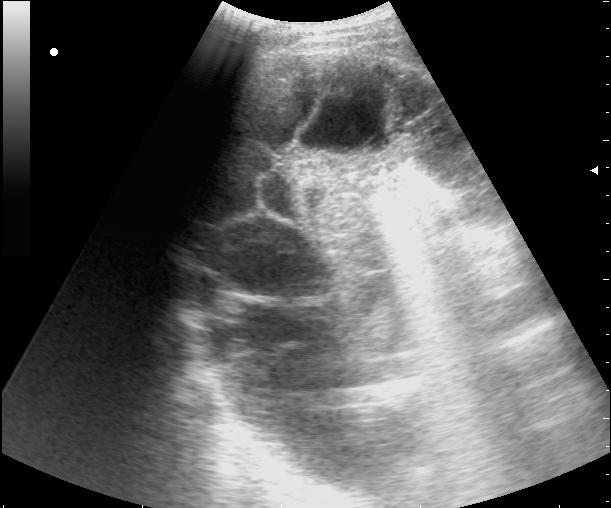

сегментарная пневмония. Экссудативный плеврит.

30788.JPG